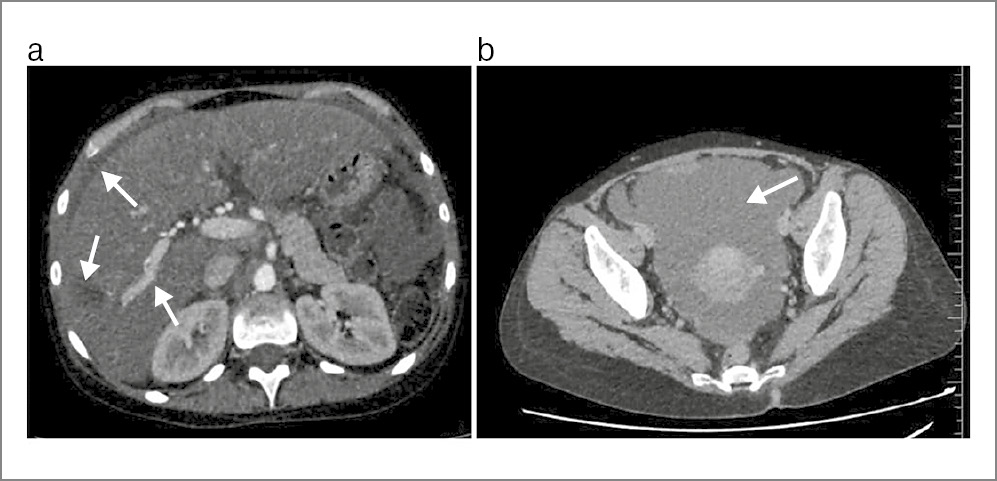

Пациентка осмотрена ответственным дежурным хирургом. Установлен диагноз: «закрытая травма живота. Гематома SVI печени. Гемоперитонеум», принято решение о выполнении симультантной операции – рентгенэндоваскулярной эмболизации и санационной видеолапароскопии (рис. 2).

Рис. 2. Этапы оперативного вмешательства: а – экстравазация контрастного вещества при ангиографии; b – ангиография аневризматически расширенной ветви правой печеночной артерии; c – эмболизация ветви 4-го порядка правой печеночной артерии эмболизационной спиралью VortX Diamond-18 3×3,3 мм.

В гибридной операционной I этапом пунктирована и катетеризирована правая плечевая артерия, выполнена целиакография: отмечается гиперваскуляризация дистального русла и аневризма диаметром до 2 мм ветви 4-го порядка правой печеночной артерии с признаками артериовенозного сброса, общая, левая, правая печеночные, левая и правая желудочные, селезеночная, диафрагмальные артерии проходимы. Диагностический катетер селективно установлен в правой печеночной артерии. При помощи микрокатетера 0,018" и проводника 0,014" в целевую артерию суперселективно проведена и установлена эмболизационная спираль VortX Diamond-18 3×3,3 мм.

На контрольных ангиограммах: правая печеночная артерия – целевая ветвь 4-го порядка не контрастируется, эффект эмболизации достигнут, отмечается неокклюзирующий спазм в ветви 2-го порядка; общая и левая печеночные артерии, селезеночная, левая и правая желудочные, диафрагмальные артерии проходимы; диссекции и экстравазации в местах вмешательства отсутствуют.